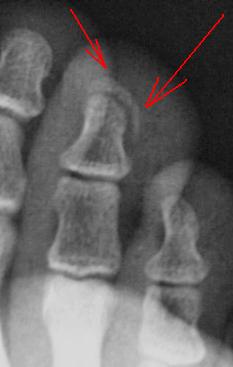

Конечно, можно говорить о подвывихе в дистальном межфаланговом суставе второго пальца.

А вот касательно 3 пальца я бы посомневался с учетом следующего:

До вроде - бы создается впечатление наличия краеаого откола костной ткани от бугристости ногтевой фаланги 3 пальца, но контур вершины ногтевой фаланги довольно ровный и четкий. Тем более, что на снимке в прямой проекции данный участок весьма плохо видно, создаемя впечатление "перебиточти " данной области.

Перелом ногтевой фаланги 3-го пальца.

Согласен, я не писал что перелома нет вообще, свежего нет. Я не стал описывать сразу, попросил пациента вернутся, он пришёл со старым снимком годичной давности, тогда был свежий перелом по типу "короны", он не сросся. Интересный снимок получился. )

На мой взгляд имеет место субкортикальный отрыв ногтевой бугристости ногтеовой фаланги 3 пальца.